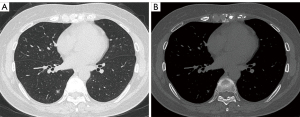

A 49-year-old Chinese man who had presented to The First Affiliated Hospital of Dalian Medical University 3 years prior with a pulmonary pure GGN on CT examination was admitted due to increased nodule density. Postadmission CT examination revealed an 8-mm mixed GGN in the right lower lung (Figure 1A). Due to high suspicion of early malignancy, it was decided that VATS right lower lung wedge resection would be performed. We used a mobile 3D C-arm system for preoperative pulmonary nodule localization because the GGN was located next to the spine and was difficult to reach and locate with the hands or surgical instruments during surgery (Figure 1B). Before implementation, we planned a localization path using the patient’s 3D-reconstructed lung images (Figure 2). The purpose of this was to reduce the time required to locate the pulmonary nodules using the mobile 3D C-arm system for the first time. Moreover, if localization had failed, we planned to perform right lower pulmonary lateral and posterior basal (S9+10) segmentectomy based on the 3D reconstruction of the lung.